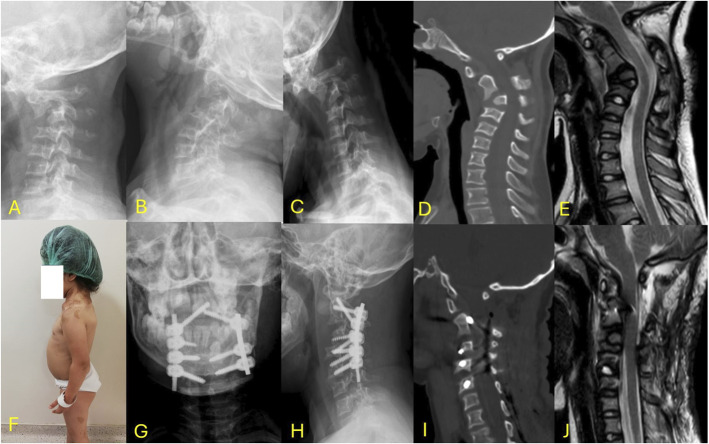

Abstract Image